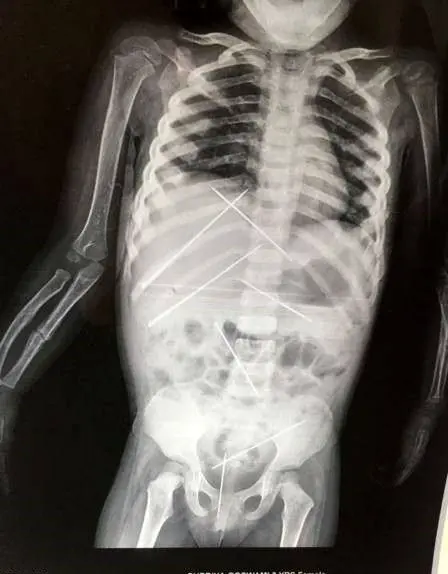

به گزارش منیبان؛ 7سوزن بدن کودک بینوا را هرلحظه تهدید می کردند تا اینکه در نهایت خطر رفع شد .تصویر وحشتناک از سی تی اسکن دختربچه 3 ساله وضعیت خطرناک او را که توسط یک جادوگر ایجاد شده بود واضح نشان داد تا پزشکان راه حلی برای نجات جان او پیش بگیرند.

پزشک بعد از معاینات اولیه سی تس اسکن کامل را تجویز کرد تا از وضعیت اعضای داخلی بیمار مطلع شود ، نتیجه ی سی تی اسکن شوکه کننده بود . وجود 7 سوزن تیز 5 سانتی متری داخل بدن دختر بچه که توسط مرد جادوگر وارد بدن کودک شده بود در موقعیت خطرناکی قرار گرفته بودند و نحوه ی قرارگرفتن سوزن ها داخل شکم او جراحی را به تاخیر انداخت .